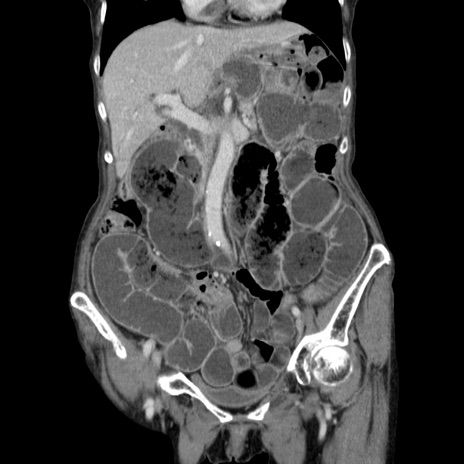

症例25(冠状断像)

【症例】80歳代女性

【主訴】胸のつかえ感

【現病歴】約9時間前に食後から胸のつかえた感じあり、嘔吐あり、来院。

【既往歴】胃癌(全摘)、胆摘、虫垂炎

【身体所見】心窩部に圧痛あり、反跳痛なし。

【データ】WBC 5700、CRP 0.05